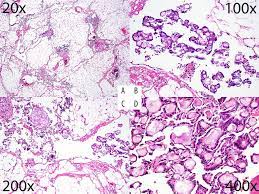

papillary mesothelioma of the ovarian surface. Although considered a tumor of uncertain malignant potential information about its biological behavior is still limited. Dr henry knipe and dr yuranga weerakkody et al. A typical morphological appearance is papillary structures with fibro vascular cores. This form of mesothelioma is a cancer that occurs in the peritoneum, or the lining of the abdominal cavity. In this subtype, the tumor cells have papillary architecture. There is very little written about. It is indistinguishable histologically from primary epithelial ovarian carcinoma:

This is a rare subtype of mesothelioma that is clinically distinct from mpm. Accurate histologic classification of these neoplasms is important for clinical management. There are three main types of ovarian tumors: L ong slender branching microvilli. These tumors tend to be small ( fig. Almost everyone who gets mesothelioma was exposed to asbestos. The peritoneum surrounds the internal organs for support and lubrication. well differentiated (benign) papillary mesothelioma of the tunica vaginalis. Primary peritoneal cystadenocarcinoma is a rare tumor of similar histogenic origin as primary ovarian carcinoma. This form of mesothelioma is a cancer that occurs in the peritoneum, or the lining of the abdominal cavity. Simultaneous occurrence of well differentiated papillary. Dr henry knipe and dr yuranga weerakkody et al. The tumor grade cannot be identified.

This is the most common form of ovarian cancer and occurs primarily in adults. The treatment for these cell types is the same as normal, but the prognosis is much worse because of the tissues from which the cells have spread. Accurate histologic classification of these neoplasms is important for clinical management. Among the epithelial, three were predominantly exophytic, papillary, well differentiated. Almost everyone who gets mesothelioma was exposed to asbestos.

This is a rare subtype of mesothelioma that is clinically distinct from mpm. The rarity of this entity and the difficulties differentiating it from either ovarian carcinoma or peritoneal mesothelioma may lead to frequent misdiagnoses and may raise some concerns about its. Immunohistochemical analysis of percutaneously obtained ascitic fluid. A typical morphological appearance is papillary structures with fibro vascular cores. This occurs primarily in children and. Often, it is an incidental surgical finding when laparatomy is done for ovarian epithelial tumours, with histological pattern of predominantly papillary well differentiated mesothelial cells, and prominent stromal infiltrate 1. Primary ovarian mesothelioma is a rare, aggressive neoplastic disease with a poor prognosis. These are dealt with in the ovarian tumours article. In general, the lower the tumor's grade, the better the prognosis. Primary peritoneal cystadenocarcinoma is a rare tumor of similar histogenic origin as primary ovarian carcinoma. papillary mesothelioma of the ovarian surface. To our knowledge, peritoneal diffuse malignant mesothelioma (mm) arising in the setting of endometriosis has not been reported. The purpose of this study is to report the.